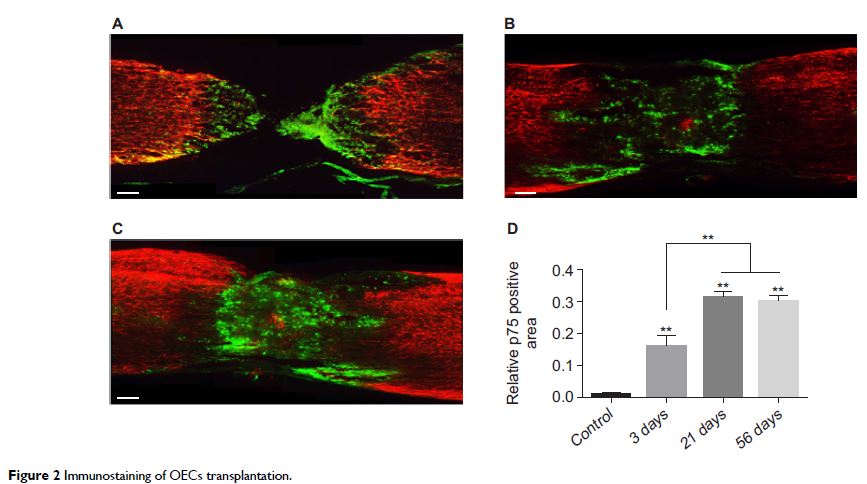

Original Research

通过腰椎穿刺对胸部脊髓损伤小鼠进行嗅鞘细胞的鞘内移植

- 作者:Tao Liu, Zhongqing Ji, Shaik Mohammed Ahsan, Yu Zhang, Peng Zhang, Zhihai Fan, Yixin Shen

- 期刊:Journal of Neurorestoratology